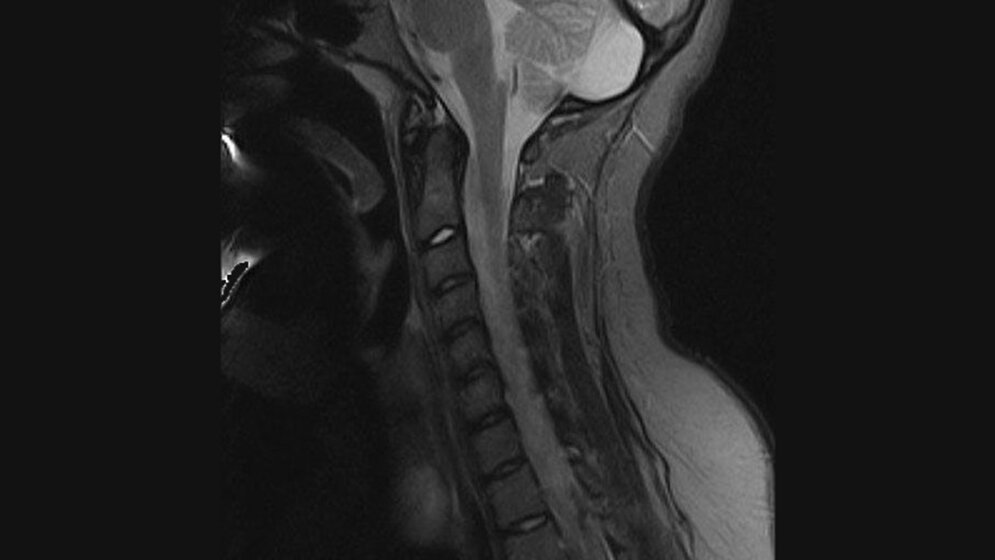

Schnittbilddiagnostik der Wirbelsäule (7.19)

Kernspintomographische Untersuchungen der Halswirbelsäule erfassen regelmäßig und obligat den kraniozervikalen Übergang. So können Strukturen der Schädelbasis, der mittleren und hinteren Schädelgrube mit beurteilt werden.